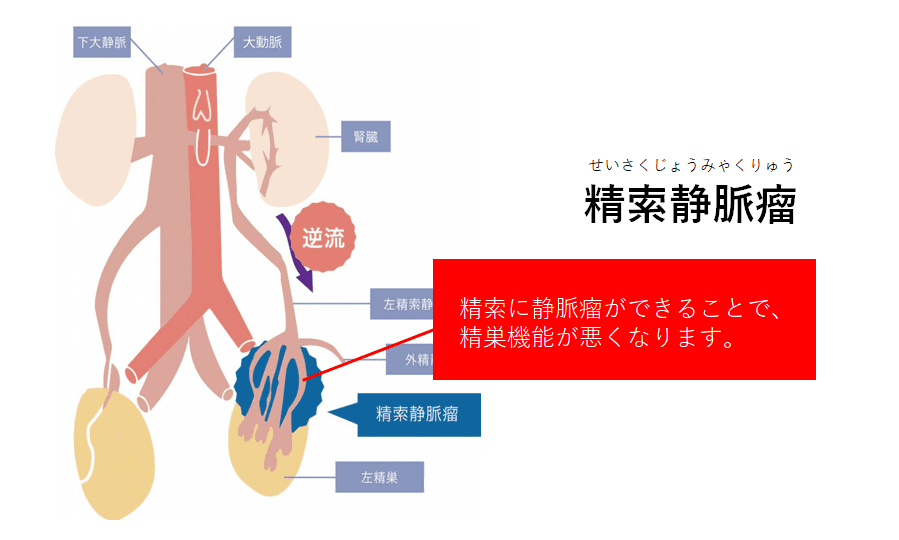

精索静脈瘤 銀座リプロ外科 東京の男性不妊治療 医療法人社団マイクロ会